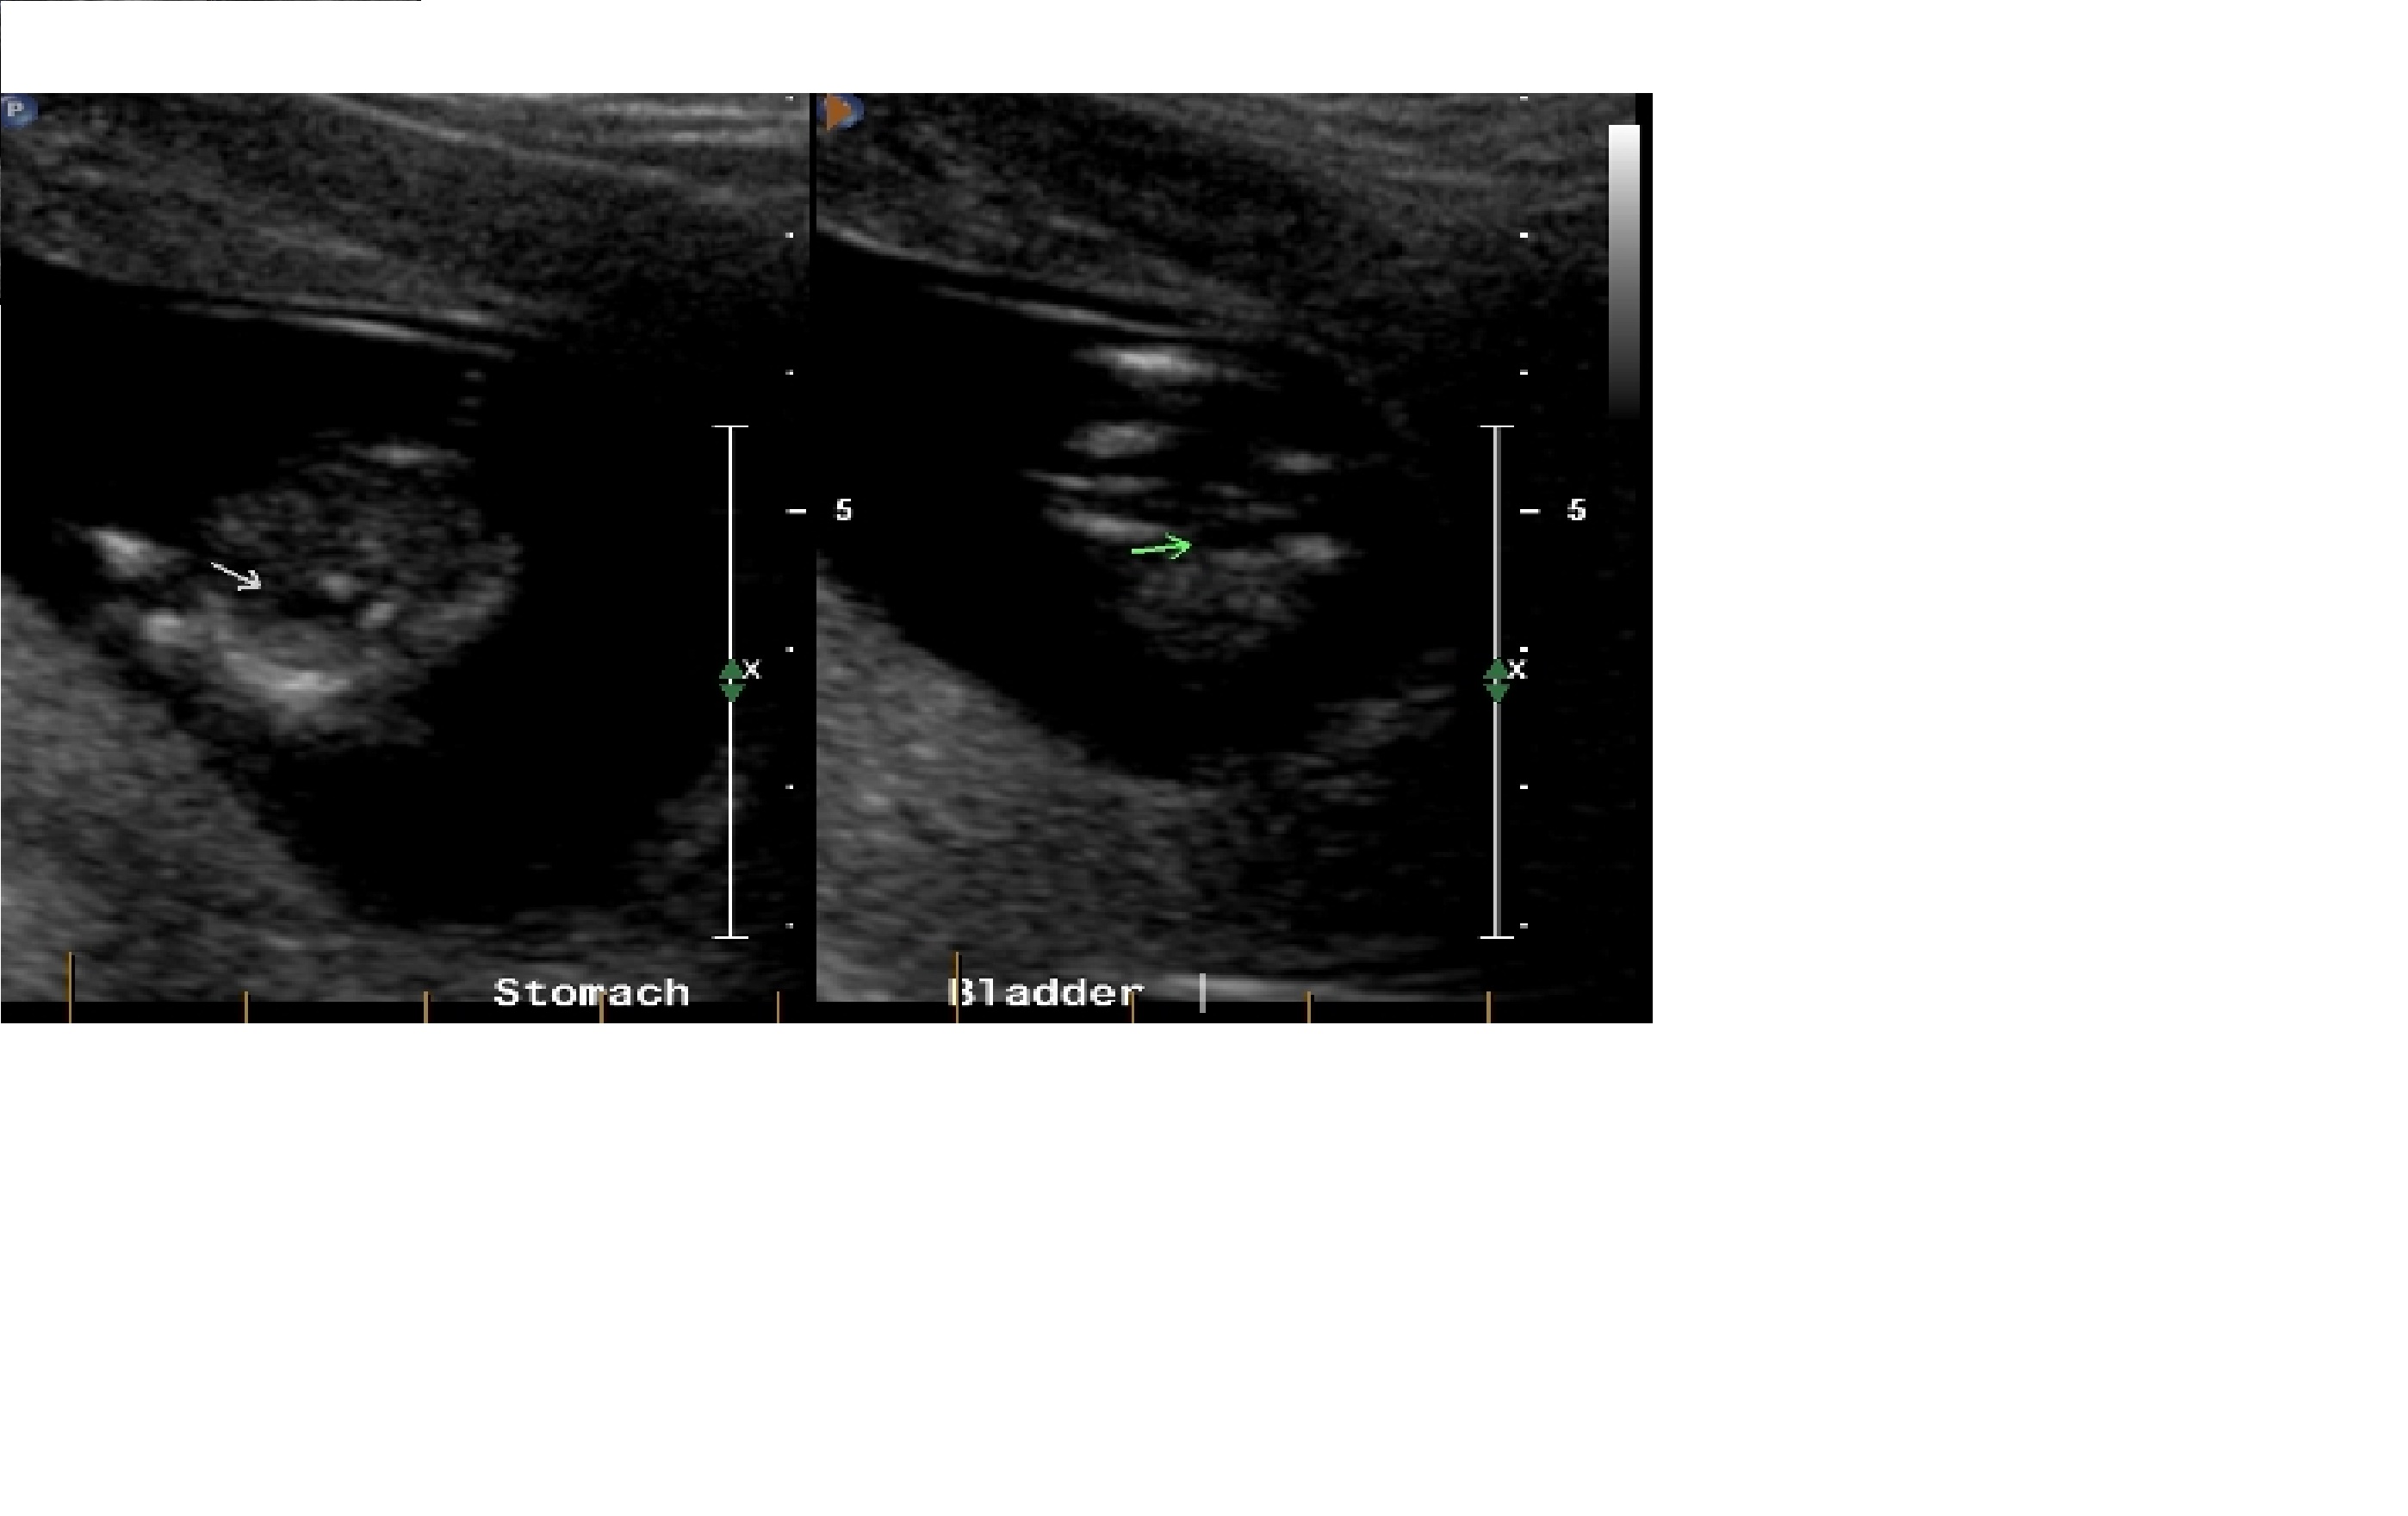

I've tried to resize the images.

And another. I hope this is clearer. Attachment 7310

Its really hard to tell, i am going to guess boy though.

Maybe a boy? That's pretty much just a guess, though.

lean boy

Boy

In the last photo it looks like there's a nub leaning upwards. I'd guess a boy if that is indeed the nub.

looks boy to me, from what I can see it seems to point up a bit